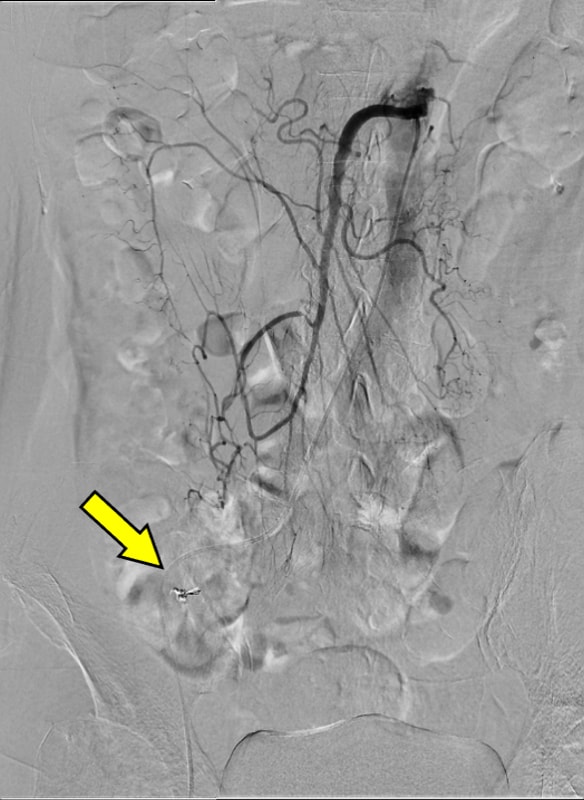

血便があり、当院消化器内科に入院となった。第3病日に下部消化管内視鏡を行うも出血源は不明であった。第4病日に再度血便があり、造影CTを施行すると上行結腸憩室からの活動性出血を認めたため、速やかに緊急TAEを施行した。血管造影で回結腸動脈の分枝からextravasationを認め、責任動脈をコイル塞栓した。術後、再出血、Hb値の低下を認めず、第13病日に退院となった。

PCCTによる高精細な画像はextravasationの検出にとどまらず、責任血管を描出することで標的血管の特定を容易にする。その結果、血管造影での探索時間が短縮され、経カテーテル動脈塞栓術(TAE)の迅速かつ確実な施行につながり、手技の成功率と効率を高めている。